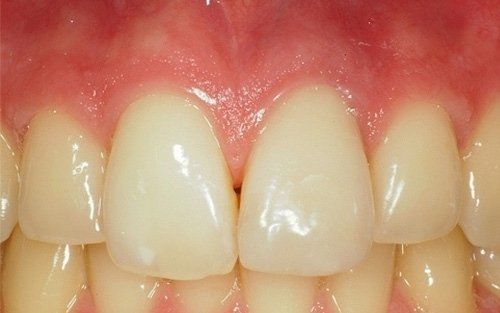

I denti da latte traumatizzati più spesso vanno incontro a necrosi con conseguente cambiamento di colore, divenendo grigiastri, segno della morte delle cellule della polpa dentaria. In altre occasioni, il dente può fratturarsi in maniera più o meno ampia: se il frammento viene ritrovato, potrà essere re-incollato in maniera invisibile, oppure verrà ricostruito con i materiali compositi.